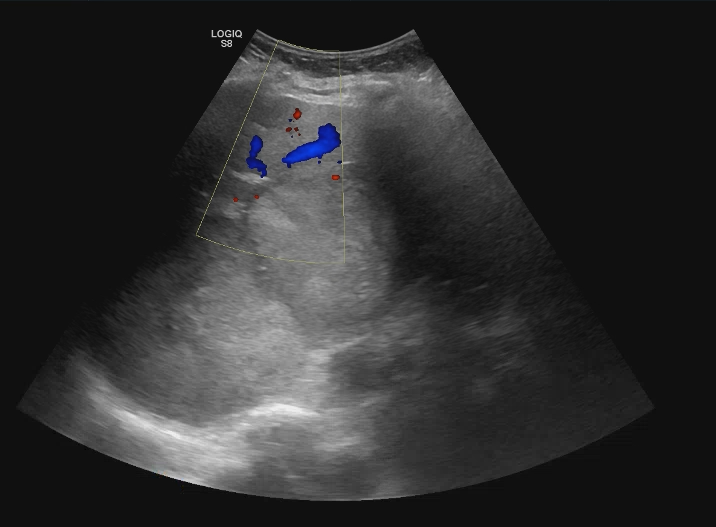

Descripción de los hallazgos ecográficos y las imágenes más relevantes para la resolución del caso

Se realiza ecografía abdominal en la consulta que muestra abundantes lesiones ocupantes de espacio en ambos lóbulos hepáticos, alguna de gran tamaño.Otras pruebas complementarias realizadas (si existen)

Hígado con múltiples metástasis y ambos lóbulos, la más gruesa de uns 10,2 cm en los segmentos VI y VII. Colecistolitiasis. Vía biliar no dilatada.Esplenomegalia con nódulos 12 y 14 mm inespecíficos. Nódulos suprarrenal izquierdo de 46 mm y dos derechos de 14 y 18 mm, inespecificos. Páncreas de medida y morfología normal. No hay signos de uropatía obstructiva. Riñones dentro de la normalidad con el nefrograma simétrico. Adenopatías retroperitoneales de predominio retrocavales y enteraortocava, la mas gruesa de 19 mm. Lesiones líticas en las costillas, esternón, vertrebrales y pelvianas. Conclusión: Enfemerdad neoplasia con diseminacion pulmonar y hepática, osea, ganglionar y probablemente esplenica y suprarrenal bilateral. No se identifica origen.

Biopsia de nódulo hepático positiva para melanoma maligno.